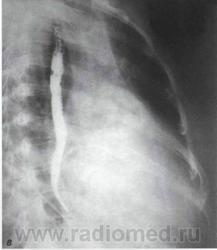

В правой передней косой проекции определяются ранние и самые выразительные признаки увеличения левого предсердия. При этом тень сердца проступает в ретрокардиальное пространство, частично или полностью занимая его, или даже накладываясь на тень позвоночника.

По мере увеличения левого предсердия пищевод, тесно прилегающий к его задней стенке, отклоняется кзади и вправо. Степень уменьшения ретрокардиаль - ного пространства, протяженность дуги и ее радиус воспроизводят форму левого предсердия и позволяют судить о степени его увеличения. При чистом или преобладающем митральном стенозе отклонение пищевода происходит по дуге малого радиуса.

Рентгенологические признаки дилатации левого предсердия в правой косой проекции с контрастированным пищеводом: а, б, в - I, II и III степени увеличения левого предсердия.

В норме ретрокардиальное пространство на уровне левого предсердия составляет не менее 3 см. При первой степени увеличения левого предсердия ретрокардиальное пространство сужено до половины. При второй степени контрастированный пищевод располагается уже в задней половине ретрокарди - ального пространства. При третьей степени тень сердца и контрастированный пищевод накладываются на тень позвоночника .

Заметно все большее отклонение контрастированного пищевода кзади и сужение ретрокардиального пространства.